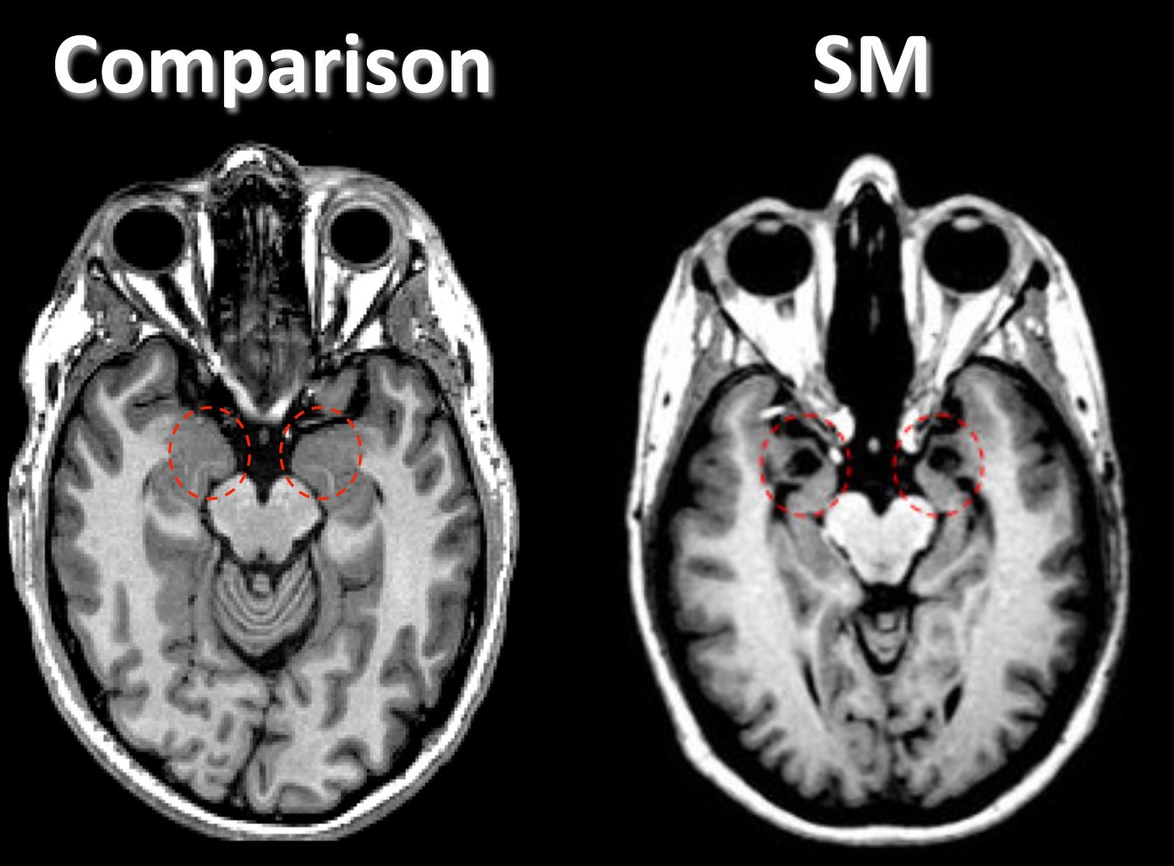

Urbach wiethe disease amygdala damage

Urbach-Wiethe disease may also present itself neurologically. In particular, the medial temporal lobes are most heavily affected by the disease. Blood vessels that feed into these brain regions can develop calcifications, and these contribute to the formation of lesions as the blood vessels harden and die. In particular, the amygdala and periamygdalar gyri are sensitive to these lesions. The amygdala is known to play a role in processing and understanding emotionally related memories, as well as processing the understanding of fear.

One patient who was studied for her neuorological damage following Urbach-Weithe disease was Patient SM. She had significant damage to her amygdala as a result of the disease. She has been an important case study towards improving our understanding of amygdala function. In the laboratory setting or in real life, she displayed no signs of experiencing fear. For example, she was taken to a haunted house as part of an experiment, and did not react to any of the surprising fearful stimuli as expected. Instead, she wanted to talk to and touch the actors who were dressed as various monsters. Patient SM, under supervision of the laboratory that was running the behavioral tests on her, went to any pet store where she was asked to hold various animals that might trigger anxiety or fear in other subjects, such as a snake and a spider. She described the experience as mostly driven by curiosity. In real life, she recalled an incident where she was held up by a man with a knife. She displayed no fear during the incident, and even returned to the same location the next day.